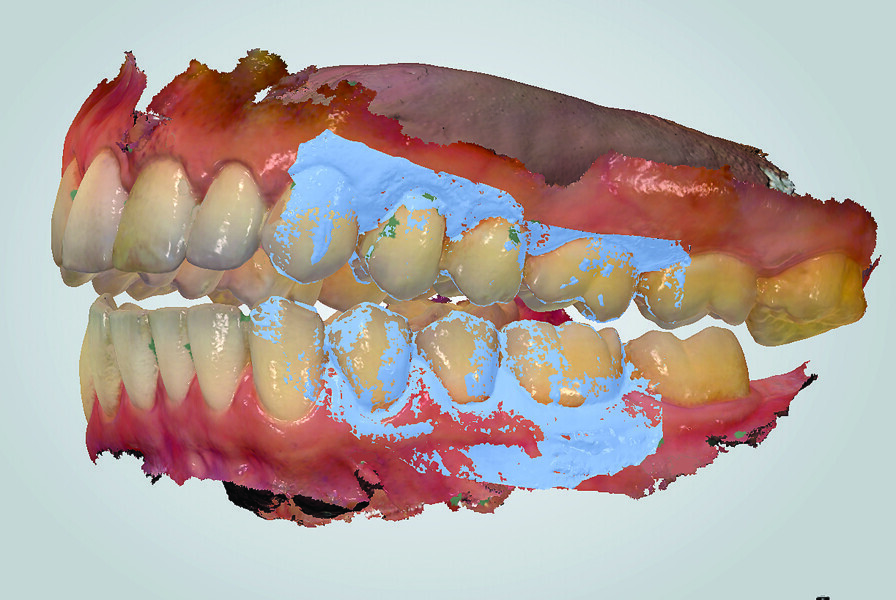

Fig. 18: TRIOS 3 software (3Shape) matching digital casts of arches to side view inter-arch scan (in light blue).